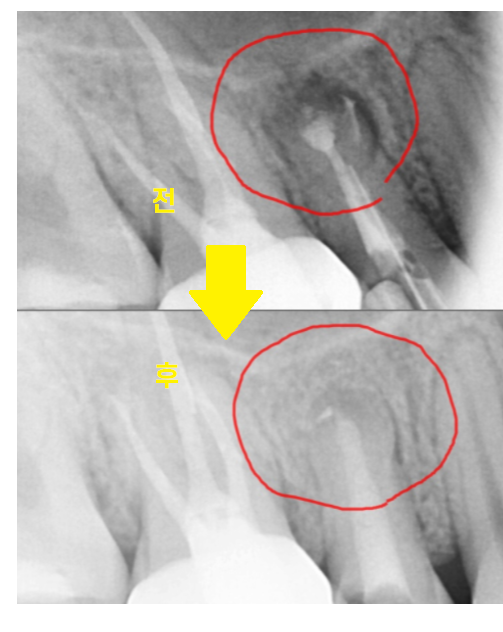

23.10.15

기존 재료를 제거하고

mta로 재신경치료 마무리 한 모습입니다.

처음 망월동 치과 방문하셨을 때는

뿌리 끝이 검정색으로

염증이 있는 상태였는데

많이 줄어든게 보이실껍니다.

한장으로 전후 차이 보여드릴께요~

잇몸에 볼록하게 물집처럼

잡혔던 염증도 사라졌죠~?

뿌리 끝 검게 잡힌 염증도

재신경치료 후

싸악 사라졌습니다!!